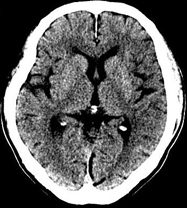

如上圖所示,相鄰的三張軸位圖像未見明顯異常,根據傳統軸位圖像很難得到準確的臨床診斷。

同一病人利用容積數據進行三維處理后,高品質MPR和三維圖像上則清晰顯示了縱向排列的腹腔干與腸系膜上動脈相鄰近,血管發生變 異,近端血管閉塞,為臨床提供了精確的診斷信息。